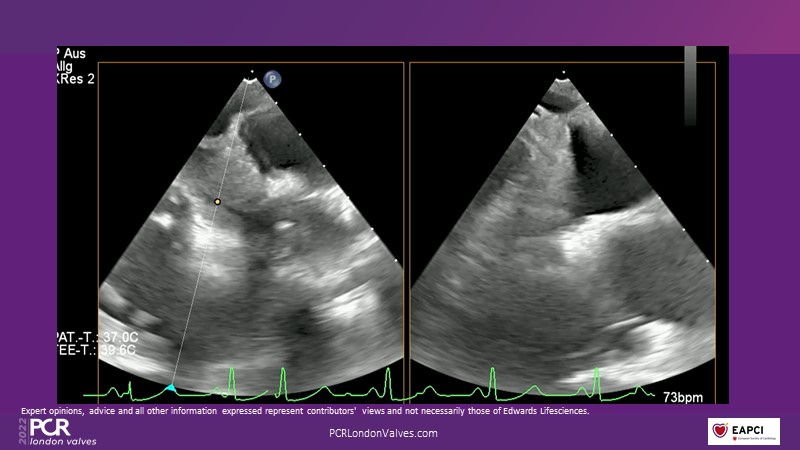

This innovative session takes you through the patient selection and anatomical characteristics when selecting amongst the different transcatheter options to treat tricuspid regurgitation, followed by a recorded demonstration using the PASCAL Precision repair system.

- To participate in a recorded demonstration using the PASCAL Precision repair system for the treatment of tricuspid regurgitation